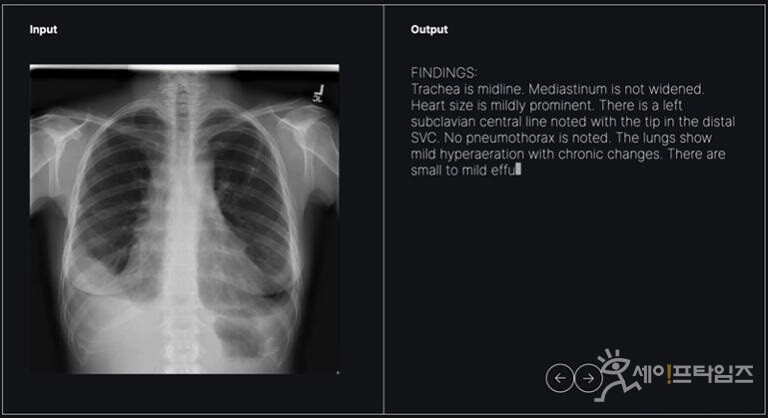

11일 제약바이오업계에 따르면 식약처는 숨빗AI의 흉부엑스레이(CXR) 초안 판독문 작성 소프트웨어 AI Read-CXR 임상시험 계획을 승인했다.

AI Read-CXR는 흉부방사선 사진 연구데이터 1400만건을 학습해 CXR에서 찾을 수 있는 다양한 소견을 영샹의학과 의료진에게 제공한다. 의료진의 주관을 배제하기 위해 자연어 입력이 불가하며 CXR 영상만 입력 가능하다.